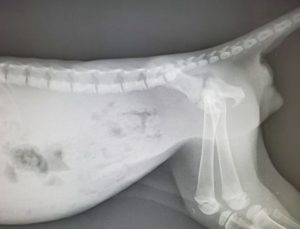

レントゲンを撮影すると、盲端になっている大腸に糞塊が停滞していました。

左が術前、右が術後1週間のレントゲン写真です。糞塊が停滞することはなくなりました。